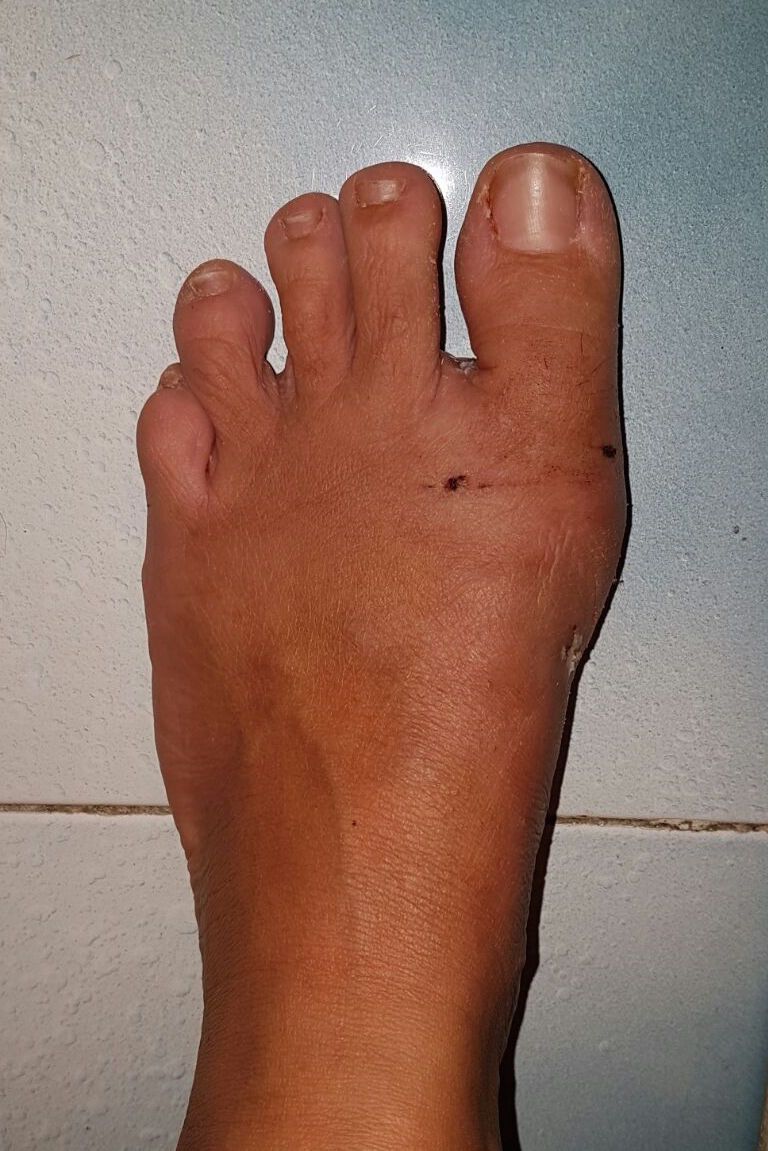

Altro campo del quale mi occupo in modo specifico è la chirurgia mini-invasiva dell'avampiede ( alluce valgo, dito a martello, metatarsalgie). Gli interventi vengono svolti con tagli molto piccoli, senza usare mezzi di sintesi definitivi (viti e camere che rimangono nel piede del paziente), favorendo una ripresa più rapida, con meno dolore per la persona e con un risultato esteticamente migliore.

Buongiorno, ho fatto delle lastre post intervento chirurgico al piede piatto sinistro dove si è riscontrato che la vite posizionata nel calcagno è leggermente uscita. Abbastanza da non riuscire a camminare o appoggiare il piede e neanche da riuscirmi a mettere o tenere un paio di scarpe. Può essere grave? Camminandoci e lavorandoci sopra può peggiorare?

Buona sera. Intanto vorrei sapere quanti anni ha. Poi sarebbe necessario sapere quando ha fatto l’intervento e vedere le radiografie.